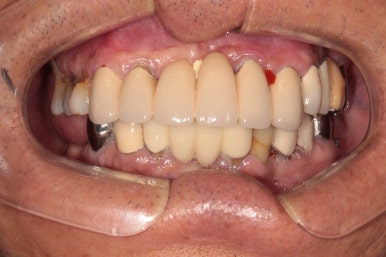

Before & After

정면 사진입니다! 사실 앞니는 가지고 계신 그대로 사용하고 있어 큰 변화가 없어 보입니다만..

상당히 가지런히 구성지게 어금니를 만들어드린 것을 보실 수 있을거에요!

우측 어금니를 보시면, 너무나 많은 치석으로 인해 만성치주염에 시달렸던 치아들은 사라지고, 이제 깔끔하게 임플란트로 대체된 것을 보실 수 있습니다.

임플란트는 보통 1 piece로 제작되기 때문에, 기존에 흔들리고 잇몸이 올라가버린 어금니보다 오히려 음식도 덜 끼고.. 사용하기 상당히 좋은 환경이 조성되었지요.